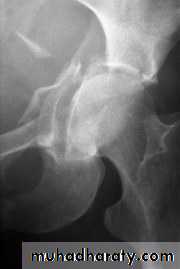

Radiological examination

two questions must be answered.

Is there a fracture?

Is it displaced ?

:Radiological classification

GRADE 1

:the femoral head is in its normal position or tilted into valgus and impacted on the femoral stump.

GRADE 2

The femoral head is normally placed and the fracture line may be difficult to diagnosed

GRADE 3

The femoral head tilted out of position and the trabecular marking are not in line with those of innominate bone.

GRADE 4

The femoral head trabeculae are normally aligned with those of innominate bone.